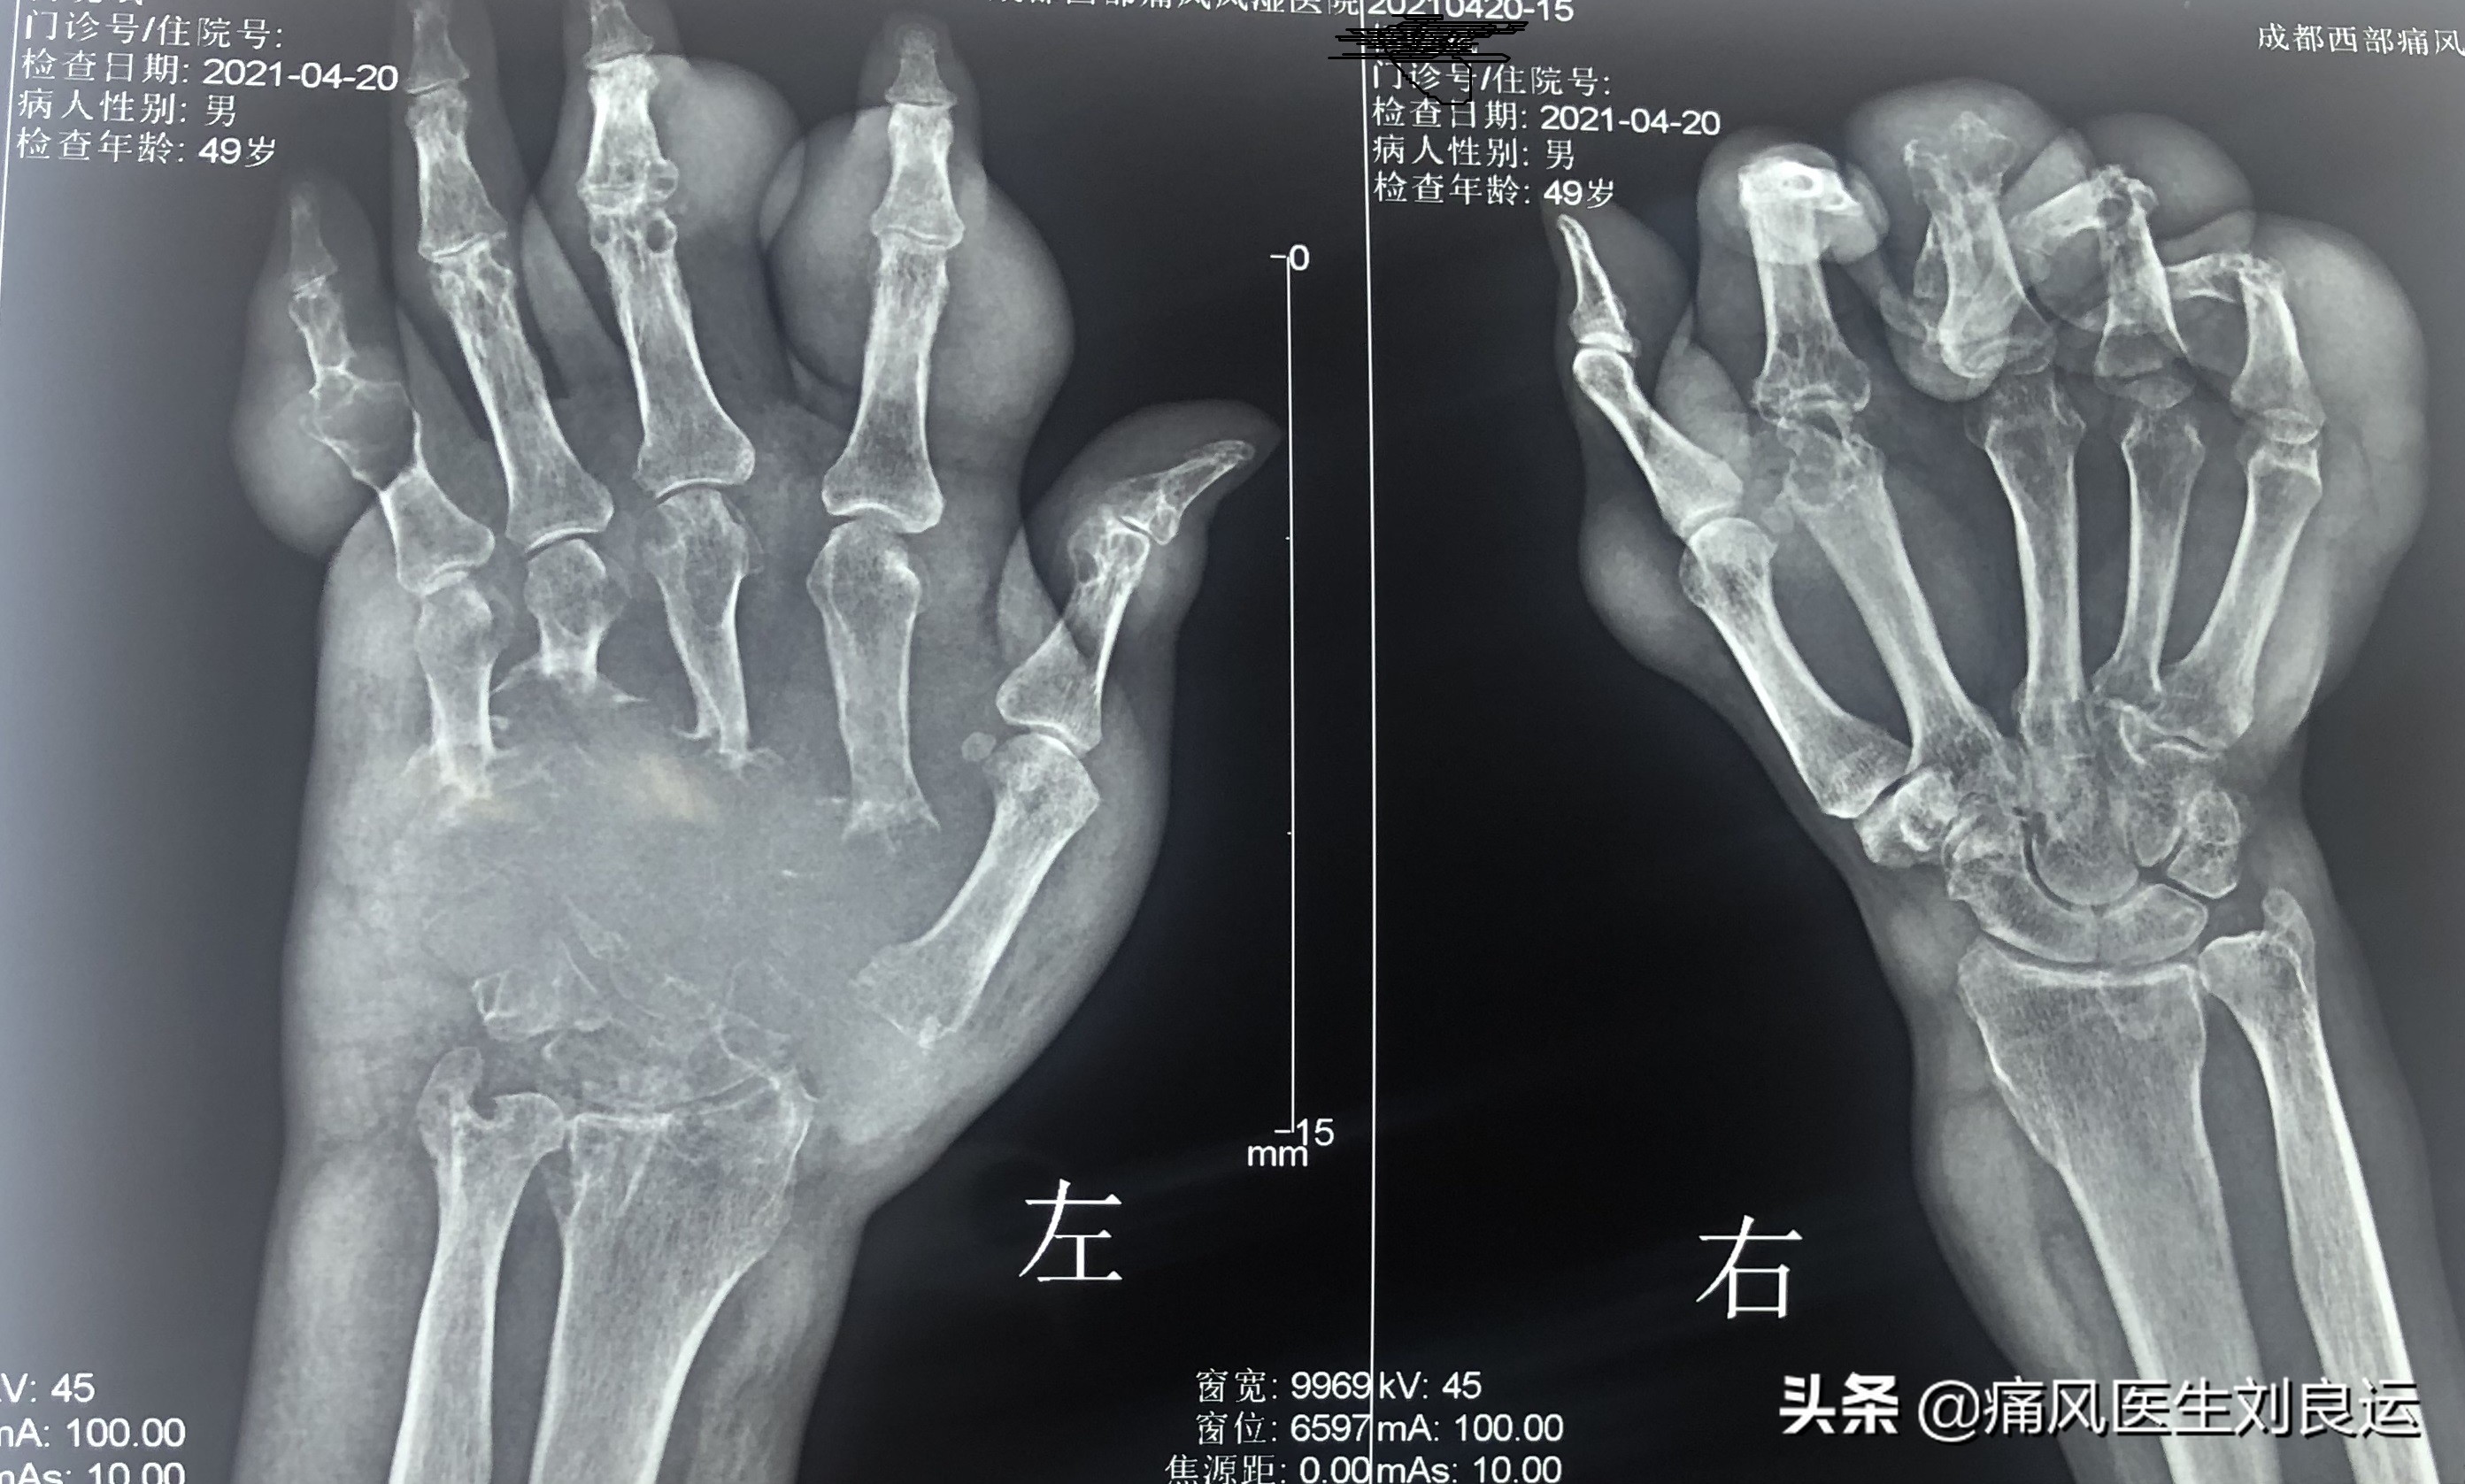

DR下手部多关节痛风石(非牟先生DR片)